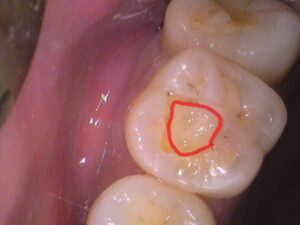

こちらの歯ですが、レジンの詰め物がされています。

赤枠で示した、ココですね!

よく見ると、

レジンが劣化したのか詰め物との間に隙間ができてきています。

歯との間に隙間ができています。